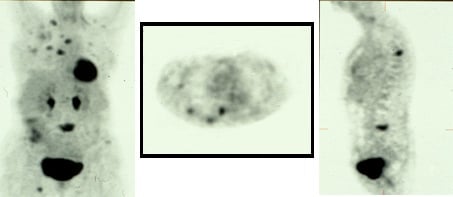

Specific tracers for NETs are 18F-DOPA PET, 11C-5HTP-PET, 68Ga-DOTA-octreotate. 18F-L DOPA and 11C-L-DOPA has been used in a number of studies to visualize NETs with a sensitivity of somewhere between 50-70%. 18F-DOPA PET has also been informative in the visualization of medullary thyroid cancer. 11C-5-HTP-PET is more sensitive than 11C-L-DOPA and also 18F-DOPA-PET particularly in endocrine pancreatic tumors. In a comparative study between CT-scan, SRS and 5-HTP-PET the latter shows significant higher sensitivity and could also demonstrate more lesions than the other methods. The draw-back with this technique is that it is only available in very few centers, such as Uppsala and Gronningen. The technique can demonstrate tumors down to 3 mm. (Fig. 5, 6).

68Ga-DOTA-octreotate-PET (Fig. 7)

68Ga is a generator-produced positron emitter, which has come more and more in to clinical praxis and is also called "the poor mans PET". In several studies it demonstrated higher sensitivity than SRS and can be done in "one-stop" procedure. The better spatial resolution by PET speaks in favour of functional imaging by PET compared with SPECT and planar imaging with SRS.

68Ga-DOTA-octreotate-PET

Somatostatin receptor scintigraphy (SRS)

SRS is a well-established functional technique for the imaging or NETs. Receptors for somatostatin and analogs have been identified on many cells of neuroendocrine origin. Of the five different subtypes of somatostatin receptors known to date, subtypes 1 and 2 appear to be the most frequent. The latter is the main target for visualization of NETs by SRS. The most commonly used somatostatin analog is octreotide, which is labelled with 111Indium, using the chelator diethylene-triamine-pentaaceticacid (DTPA) to produce 111Indium-DTPA-octreotide which is available as a commercial product - Octreoscan®. Other tracers are 111Indium-DOTA-TOC, 111Indium-DOTA-NOC and 111Indium-DOTA-TATE.

Somatostatin receptor scintigraphy (SRS)  Somatostatin receptor scintigraphy (SRS)